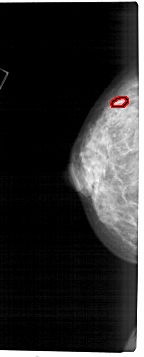

FILE: A_1283_1.LEFT_CC.OVERLAY

TOTAL_ABNORMALITIES 1

ABNORMALITY 1

LESION_TYPE CALCIFICATION TYPE PUNCTATE DISTRIBUTION CLUSTERED

ASSESSMENT 4

SUBTLETY 1

PATHOLOGY MALIGNANT

TOTAL_OUTLINES 1

BOUNDARY